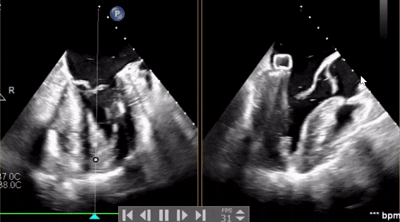

術(shù)中操作

全麻后,在心前區(qū)的肋間切開(kāi)3-4CM小切口,暴露心臟的心間位置,將二尖瓣夾合系統(tǒng)送入左心房,順利到達(dá)病變二尖瓣區(qū)域。在經(jīng)食道超聲輔助下,術(shù)者通過(guò)反復(fù)評(píng)估二尖瓣反流位置、抓捕位置、反流程度,最終在3區(qū)位置垂直于二尖瓣閉合線方向進(jìn)行巧妙?yuàn)A合最終植入1枚ValveClamp®MVC-Ⅱf夾。手術(shù)中導(dǎo)管操作時(shí)間僅30min,共夾合2次。患者術(shù)后反流程度從大量轉(zhuǎn)至微量,手術(shù)取得圓滿成功。

手術(shù)步驟

1.心尖穿刺送入16F鞘后,順著鞘管送入跨瓣器,跨瓣器跨瓣進(jìn)入左房沿著導(dǎo)絲送入擴(kuò)張器及16F鞘,撤出擴(kuò)張器和導(dǎo)絲;

2.16F鞘順著跨瓣器送入左房后,撤出跨瓣器;

3.在心房打開(kāi)上下夾;

4.3D圖像調(diào)整夾子位置及鐘向;

5.下夾撤入心室后,捕獲夾合瓣葉,第一次夾合位置為3區(qū),夾合后2區(qū)一側(cè)殘余反流量2+,不符合術(shù)前預(yù)期,推開(kāi)上下夾;

6.調(diào)整夾子軸向后再次夾合,夾合后剩余反流量1+,符合術(shù)前預(yù)期,解離上下夾。

術(shù)中剪影